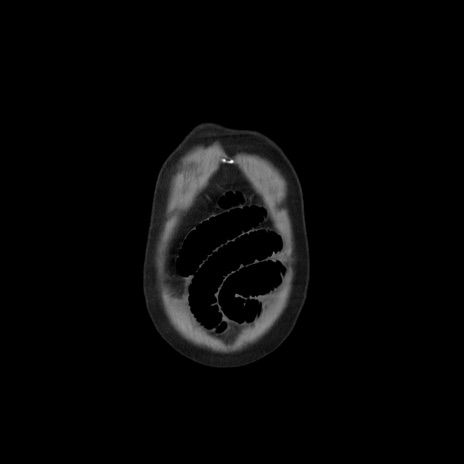

横断像